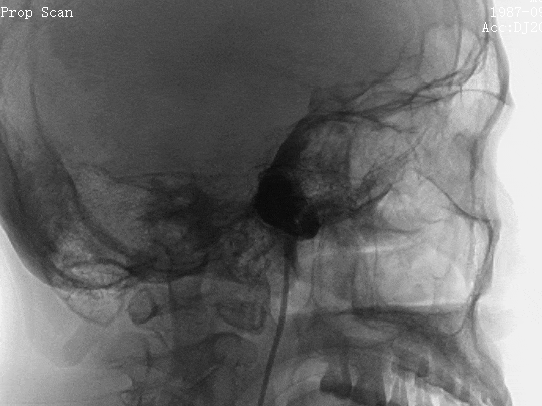

外院DSA

本院高分辨磁共振:3D-SPACE血管壁成像示右侧颈内动脉海绵窦段动脉瘤,动脉瘤壁不均匀稍增厚并强化,管腔内部分血栓形成。

动脉瘤测量:右侧颈内动脉C4段动脉瘤,大小约26.93*27.18*21.39mm;动脉瘤远端流出道明显迂曲,直径3.51mm;近端载瘤动脉路径也有迂曲,直径5.12mm;病变范围约52mm。

患者取平卧位,全身麻醉后,行右侧桡动脉穿刺,建立治疗通路。3D造影证实右侧颈内动脉C4段动脉瘤,形态不规则。